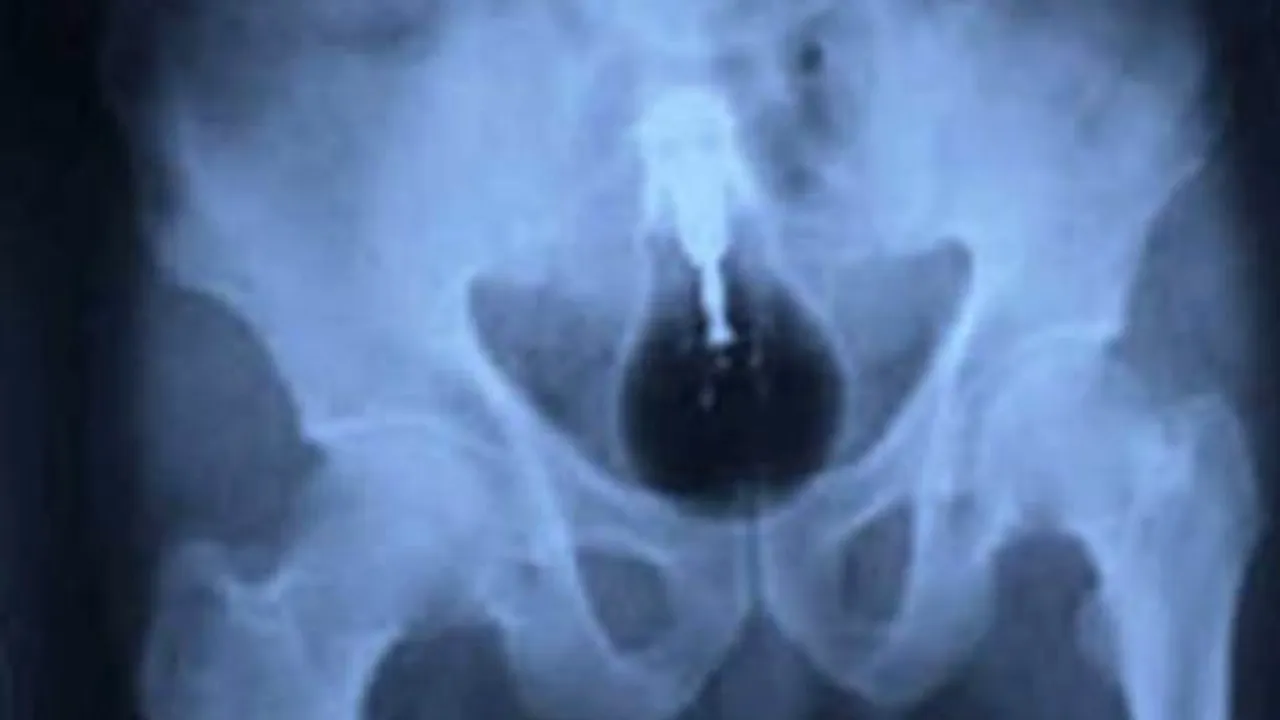

2. Magneți. Pe multe jucării este scris un avertisment cu privire la pericolul înghițirii lor. Înghițirea magneților produce serioase probleme intestinale, care pot deveni fatale daca nu sunt tratate rapid și în mod corespunzător. Un puști care a înghițit mai multe jucării magnetice a avut mult de suferit. Imaginile radiografiei demonstrează acest lucru.